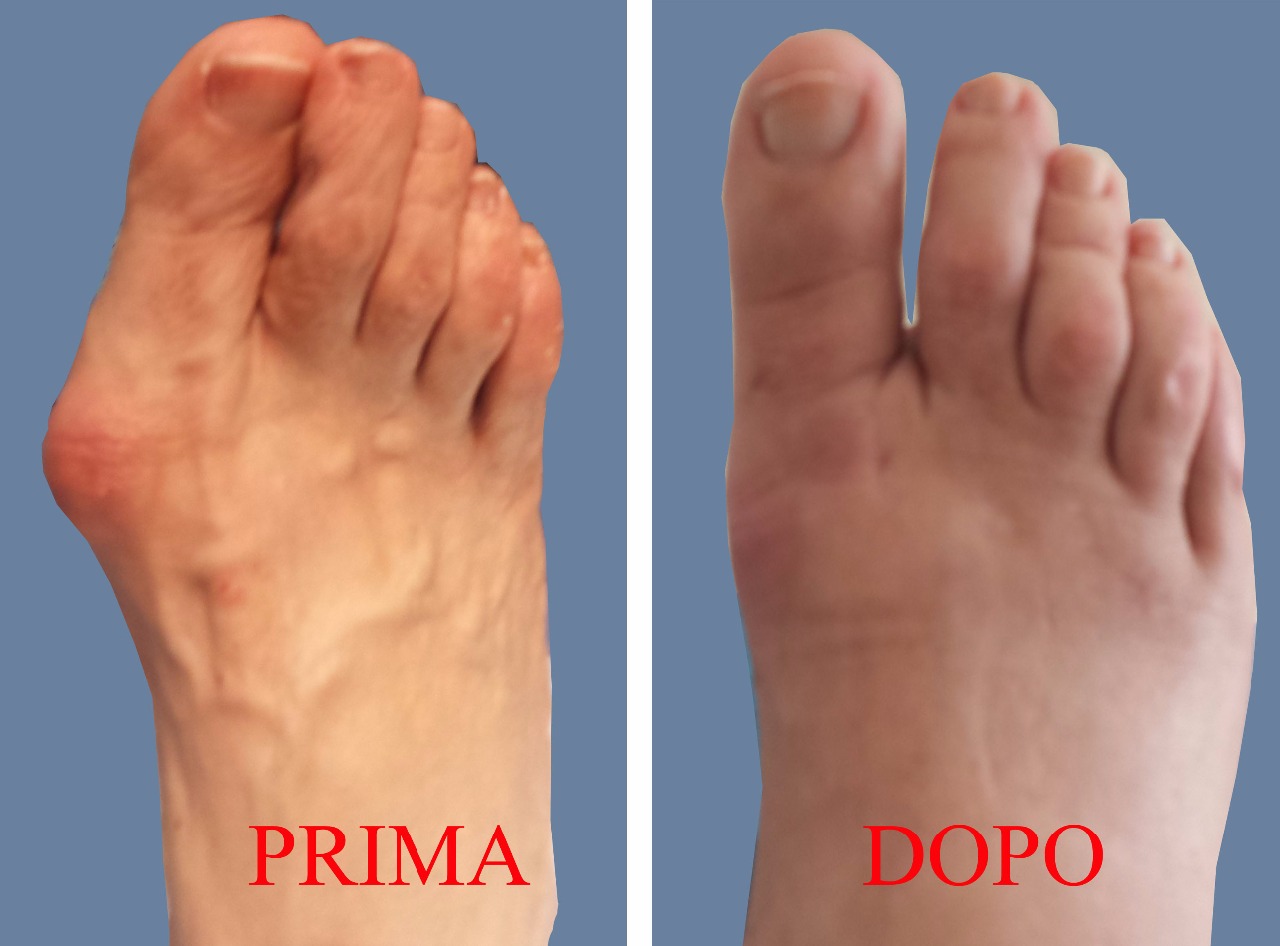

L’Alluce valgo è una deformità del piede che consiste in un’inclinazione dell’alluce (il primo dito del piede) verso le altre dita con la contemporanea deviazione del primo osso metatarsale ( che si articola con l’alluce) verso l’interno. Si crea quindi una deformità a zig zag che accorcia ed allarga il piede e determina la tipica sporgenza ossea chiamata esostosi o più comunemente “cipolla” la quale provoca una serie di non trascurabili conseguenze come arrossamento, dolore, infiammazioni (borsiti) e talvolta ulcerazioni, e rende sempre più difficile camminare normalmente ed indossare calzature di qualsiasi genere.

In genere, all’inizio si tratta di una semplice (anche se non piacevole) questione estetica ma successivamente subentra l'insufficienza funzionale dell'alluce

Inoltre, l’alluce inclinandosi lateralmente determina una spinta sulle dita esterne che risultano quindi progressivamente deviate verso l'esterno e costrette a trovare un loro spazio sollevandosi ( iperestensione) con lussazione progressiva dell’articolazione metatarso-falangea. Tale deformità delle dita denominata o “a martello” o “ad artiglio” aggravano maggiormente il sovraccarico delle teste metatarsali

A lungo andare la deviazione e l’insufficienza funzionale dell’alluce può portare a callosità e ulcerazioni nella parte anteriore del piede in corrispondenza delle teste metatarsali, tali da provocare un dolore cosi intenso da impedire l’uso di calzature o, nei casi più gravi, l’appoggio del piede. Inoltre, la deformazione progressiva del piede, oltre a generare dolori, determina un appoggio alterato e un’alterazione del passo che può avere ripercussioni serie su altre strutture, quali ginocchia, anche e colonna vertebrale.

Fino ad oggi la tecnica chirurgica prevedeva incisioni che portavano allo scoperto il metatarso, con l'inserimento di viti, fili di acciaio o di placchette: tutto questo richiedeva una convalescenza più lunga, con un certo rischio di infezioni.

Recentemente abbiamo adottato le nuove tecniche miniinvasive percutanee, che danno ottimi risultati, a patto che vengano usate nei casi in cui vi è la giusta indicazione e non indiscriminatamente.

Si tratta di una tecnica percutanea ossia attraverso dei buchini della cute, e sotto il controllo di uno strumento radiologico (amplificatore di brillanza o fluoroscopio), il chirurgo manovrando delle minifrese, simili al trapano del dentista, può eliminare la dolorosa prominenza (esostosi) e, tramite delle osteotomie, riallineare l´alluce, correggere le metatarsalgiee e le dita a martello.

Con un’unica operazione chirurgica senza tagli e senza impiego di mezzi di sintesi ( viti, chiodi, cambre o fili di ferro) si può risolvere per sempre tutte le problematiche variamente connesse alla presenza dell’alluce valgo, ripristinando la corretta funzionalità della deambulazione permettendo al paziente di tornare a indossare calzature normali.

Nessuna cicatrice o punti di sutura sulla pelle. Dopo l’operazione viene confezionato solo un particolare bendaggio che mantiene una valida e giusta correzione.

L’introduzione della tecnica percutanea mini invasiva e delle nuove tecniche anestesiologiche, con l’uso di anestetici a lunga durata d’azione, permette, rispetto alla tecniche tradizionali, un intervento meno invasivo, di più facile guarigione e soprattutto comporta un buon controllo del dolore . Molti pazienti si stupiscono di aver sofferto poco o di non aver sofferto affatto.

La tecnica percutanea riduce di gran lunga tali complicazioni, specialmente quelle infettive, in quando non “apre il piede” e non usa mezzi di sintesi .